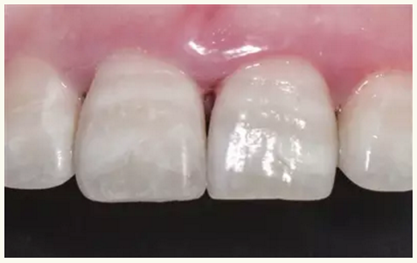

牙體樹脂美學(xué)修復(fù),顧名思義,指的是以復(fù)合樹脂為充填材料,按照美學(xué)的要求對(duì)牙體缺損進(jìn)行修復(fù)?;仡櫄v史,復(fù)合樹脂粘結(jié)修復(fù)技術(shù)發(fā)展至今已有一個(gè)甲子的歷史。60年來,樹脂材料不斷推陳出新,粘結(jié)技術(shù)持續(xù)進(jìn)步革新,樹脂修復(fù)因其優(yōu)良的物理機(jī)械性能,便利的操作性和卓越的美觀性而日益得到臨床醫(yī)生的青睞,成為臨床上進(jìn)行牙體缺損修復(fù)首選的材料和技術(shù)。而隨著人們物質(zhì)生活水平的不斷提高,患者對(duì)修復(fù)的效果美學(xué)要求也在不斷提高,強(qiáng)有力地推動(dòng)了樹脂粘結(jié)修復(fù)技術(shù)的快速前進(jìn)。尤其是近幾年,伴隨著材料和技術(shù)的發(fā)展,美學(xué)修復(fù)的理念深入人心。因此,當(dāng)復(fù)合樹脂粘結(jié)修復(fù)技術(shù)與口腔醫(yī)學(xué)美學(xué)相互融合滲透,最終發(fā)展成了牙體樹脂美學(xué)修復(fù)技術(shù)。

牙體樹脂美學(xué)修復(fù)適用于對(duì)牙體修復(fù)效果有美學(xué)要求的前牙或者后牙。對(duì)于患者而言,前牙修復(fù)效果更為直觀。因此,臨床上對(duì)于前牙美學(xué)修復(fù)的需求更為迫切,常見的修復(fù)類型為及切角的前牙牙體缺損。治療的過程一般為①比色、②缺損牙體的樹脂預(yù)修復(fù)(直接修復(fù))或者取模翻制石膏模型的基礎(chǔ)上制作蠟型恢復(fù)缺損牙體(間接修復(fù)),③硅橡膠制作舌側(cè)導(dǎo)板,④上橡皮障,牙體預(yù)備(洞緣斜面),⑤酸蝕、粘結(jié),⑥樹脂分層充填,⑦修形、拋光,⑧完成。

▲術(shù)后即刻(唇側(cè))

▲術(shù)后一月(唇側(cè))